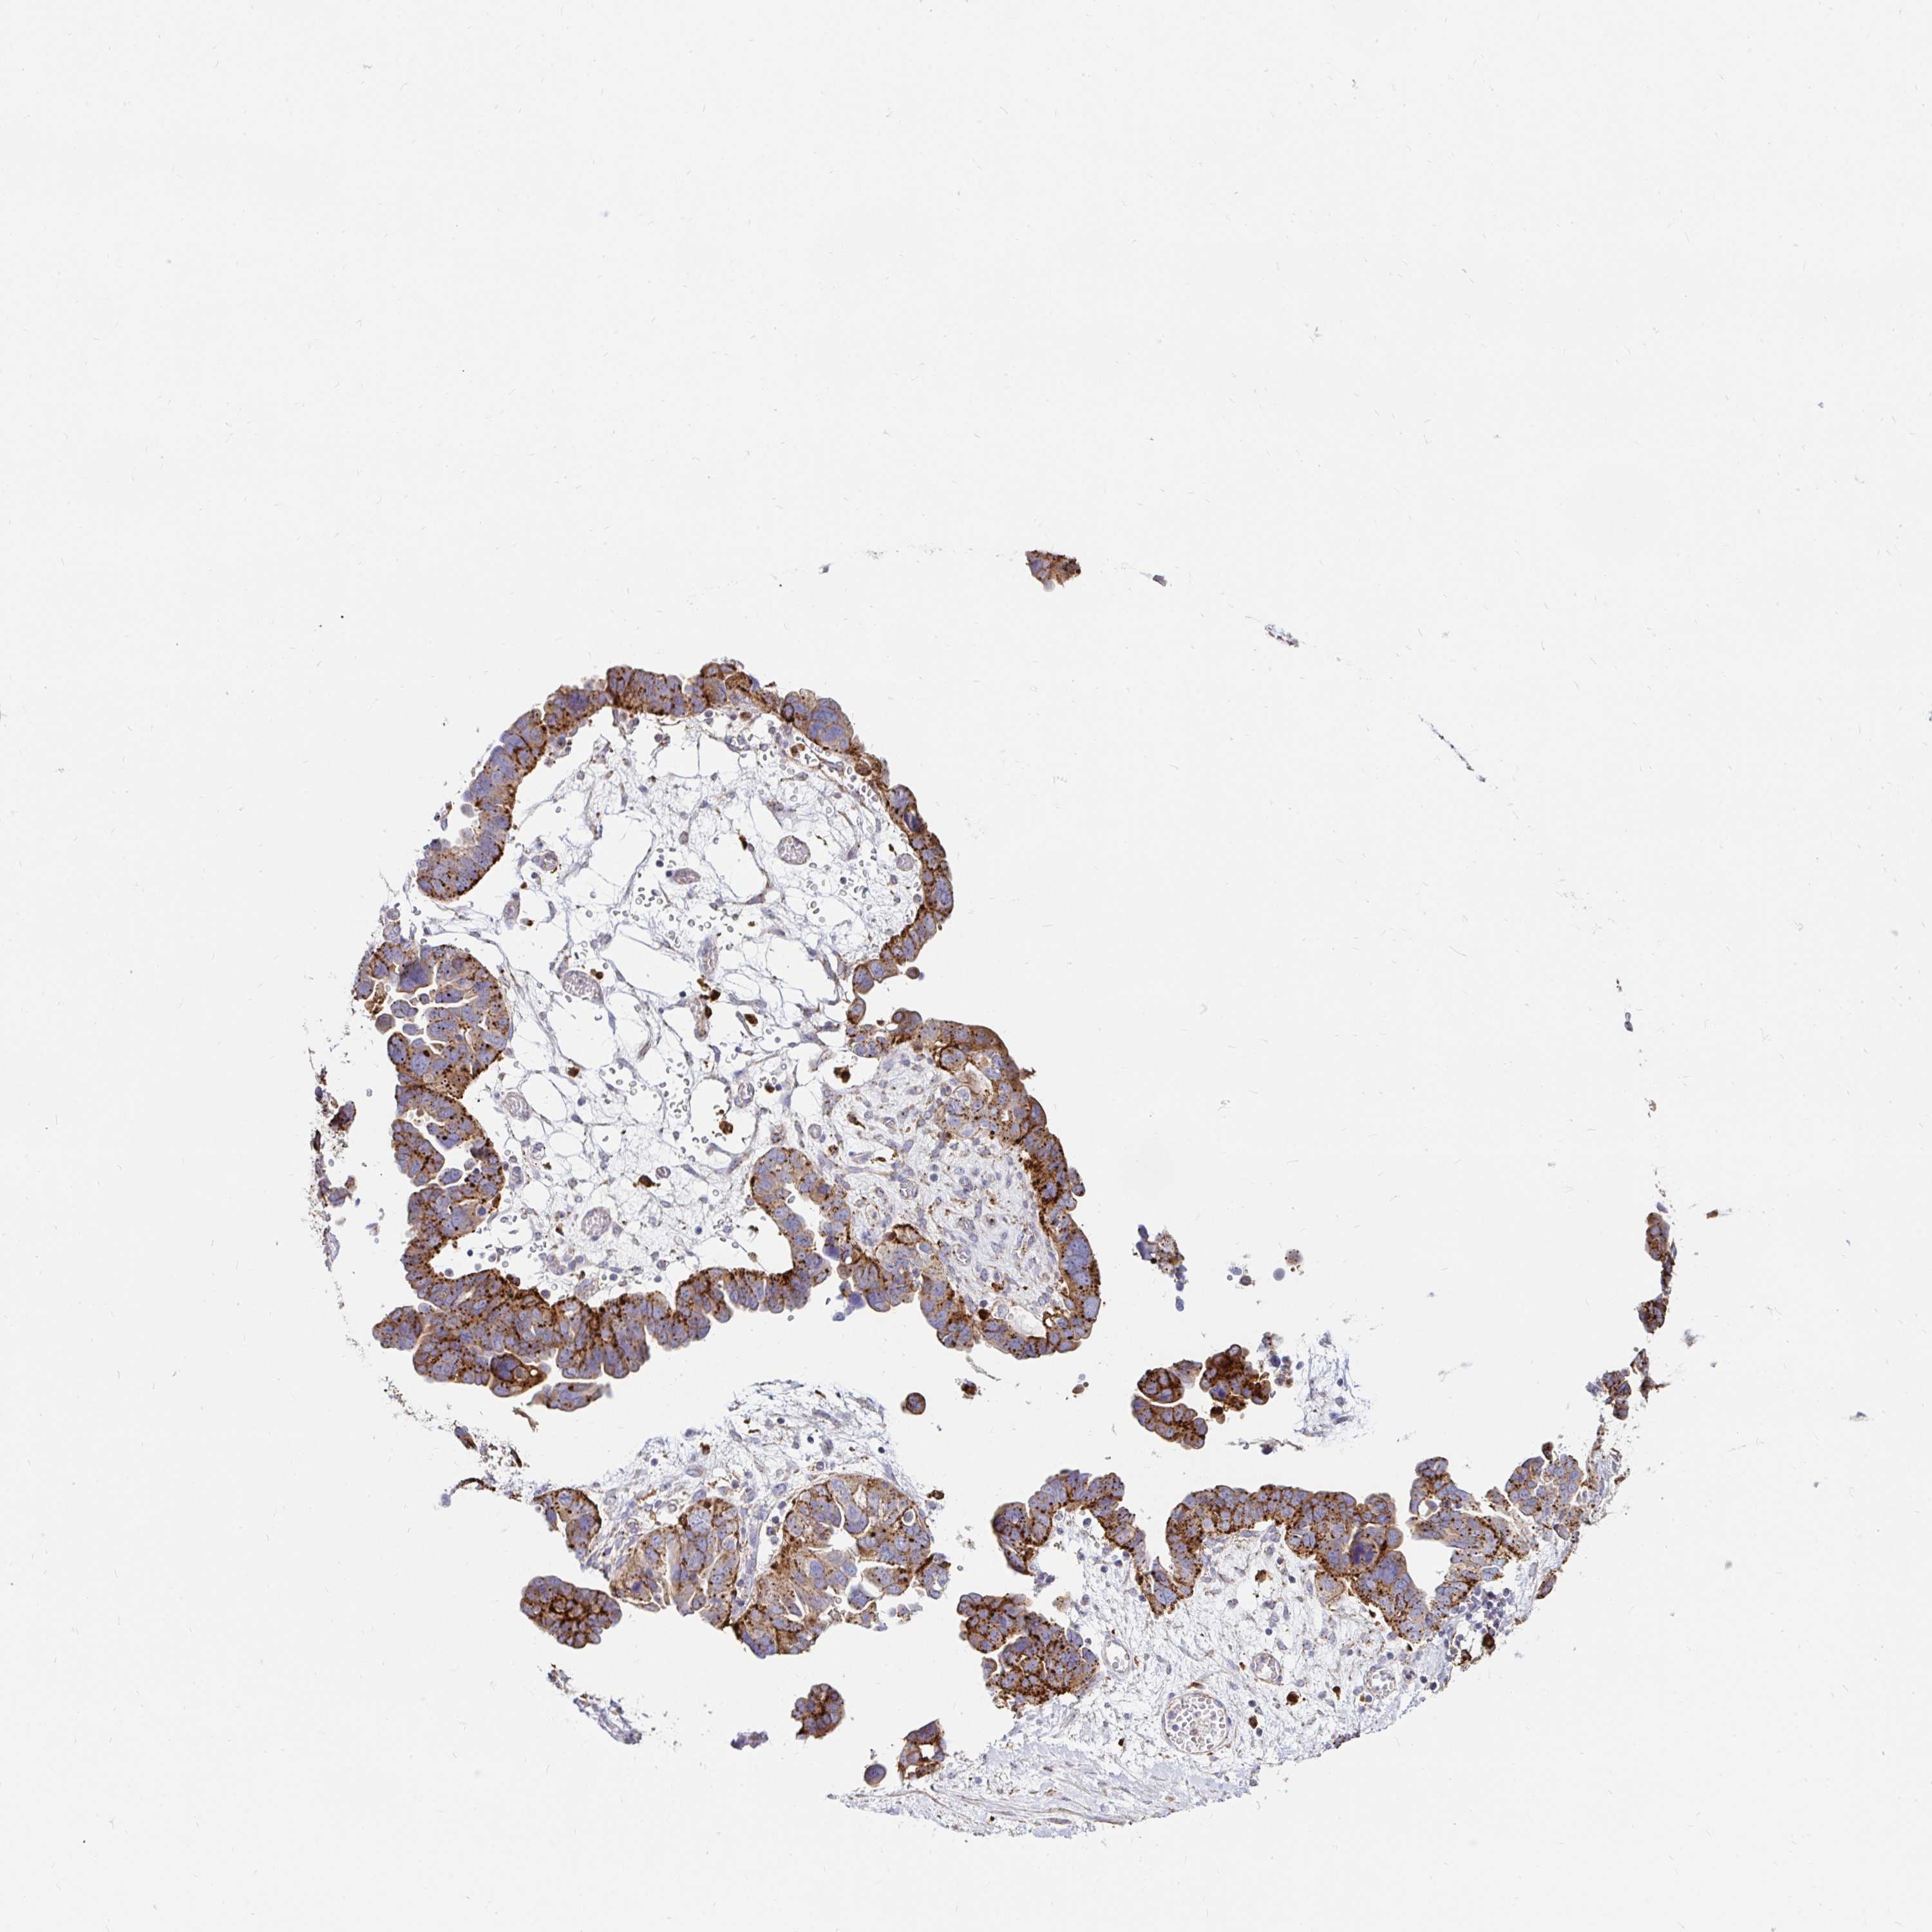

OVARIAN CANCER - Protein expressioni

A mouse-over function shows sample information and annotation data. Click on an image to view it in a full screen mode. Samples can be filtered based on level of antibody staining by selecting one or several of the following categories: high, medium, low and not detected. The assay and annotation is described here.

Note that samples used for immunohistochemistry by the Human Protein Atlas do not correspond to samples in the TCGA dataset.

Antibody stainingi

Antibody staining in the annotated cell types in the current human tissue is reported as not detected, low, medium, or high, based on conventional immunohistochemistry profiling in selected tissues. This score is based on the combination of the staining intensity and fraction of stained cells.

Each image is clickable and will lead to virtual microscopy that enables deeper exploration of all samples and also displays staining intensity scores, fraction scores and subcellular localization as well as patient and tissue information for each sample.

Antibody HPA046542

Antibody HPA056371

Staining

High

Medium

Low

Not detected

Intensity

Strong

Moderate

Weak

Negative

Quantity

>75%

75%-25%

<25%

None

Location

Nuclear

Cytoplasmic/membranous

Cytoplasmic/membranous,nuclear

Cystadenocarcinoma, serous, NOS

Carcinoma, NOS

Cystadenocarcinoma, mucinous, NOS

Carcinoma, endometroid